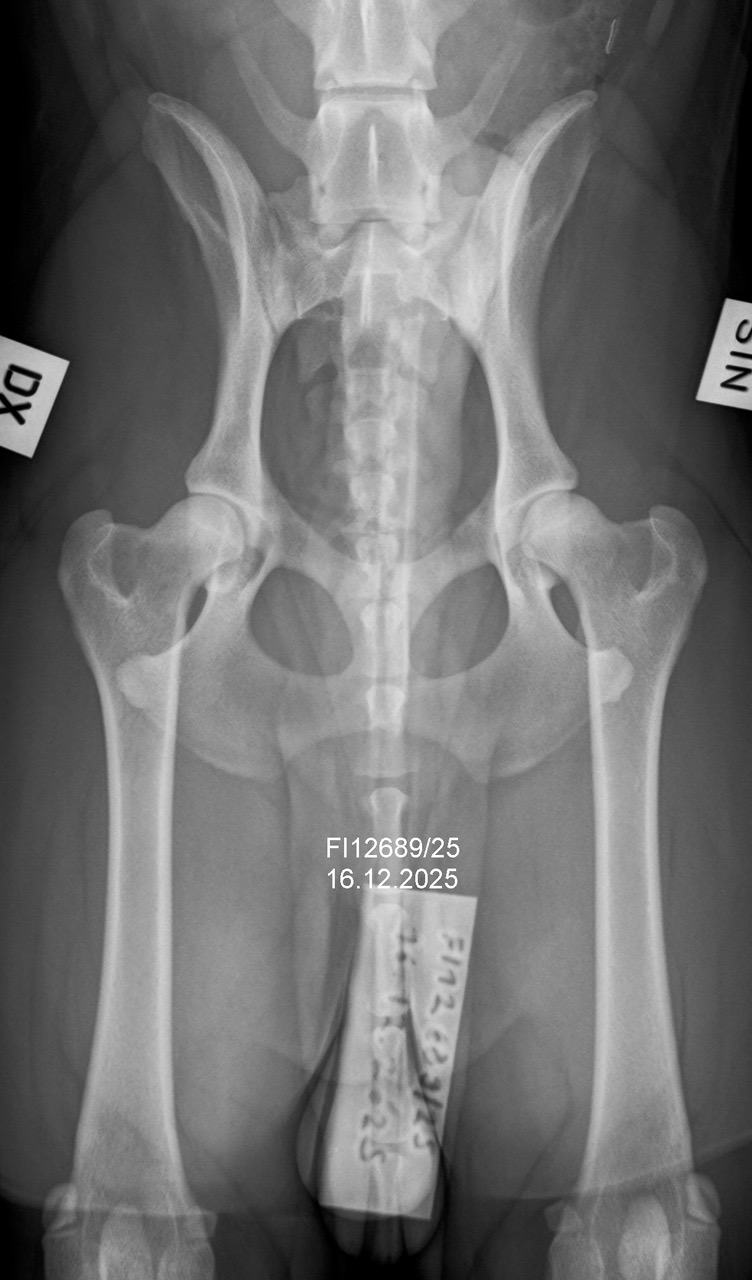

Keplerin viralliset luustokuvat

Kepler kävi kolmen sisaruksensa kanssa luustokuvilla tiistaina. Toki jo välikuvien perusteella tiesin melko hyvin mitä voi odottaa, joten niin paljoa ei jännittänyt, mutta toki silti vähän. Kuvat näytti kuitenkin oikein hyvältä, joten lausuntoja saattoi jäädä odottamaan levollisin mielin. Tänään tuli sitten viralliset tulokset, ja hienoltahan ne...